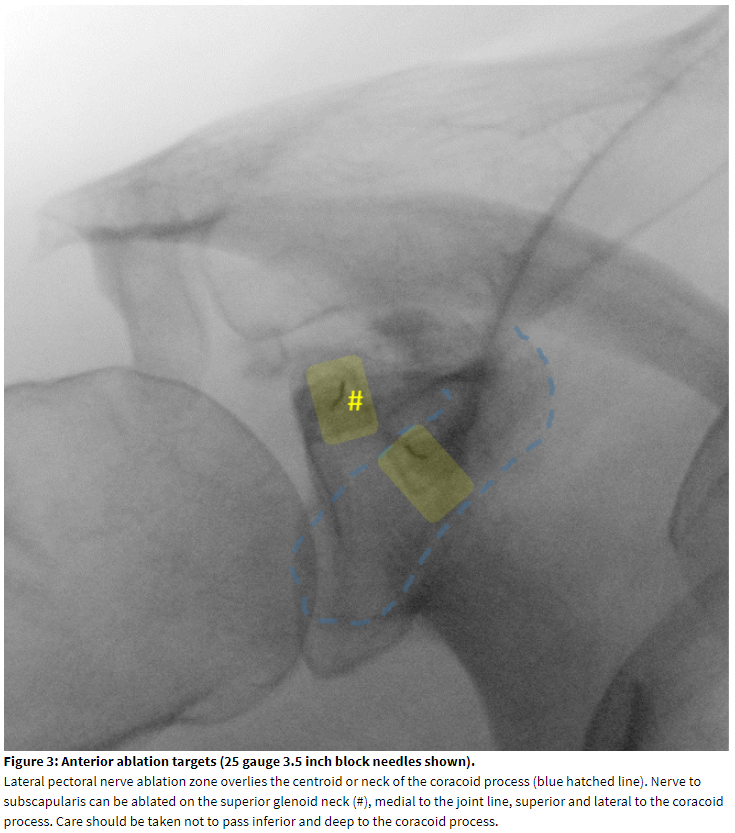

Chronic shoulder joint pain is the third most common musculoskeletal complaint. It is a common and burdensome condition, with an estimated prevalence of 7-26%.[1] The shoulder joint has the most complex range of motion of the major joints. The shoulder girdle, which connects the upper extremity to the thorax, includes four joints or articulations: 1) the glenohumeral joint, 2) the acromioclavicular joint, 3) the sternoclavicular joint, and 4) the scapulothroacic articulation. The bones that comprise these structures include the humerus, scapula, and clavicle, and the joint also relies on dynamic stabilization from the muscles of the rotator cuff (supraspinatus, infraspinatus, teres minor, subscapularis). Hilton’s law of joint innervation, which has been validated[2] and has stood the test of time since 1863, predicts potential nerve supply to the joints of the shoulder by accompanying muscle innervation. The structures and potential nerves are summarized in Table 1.